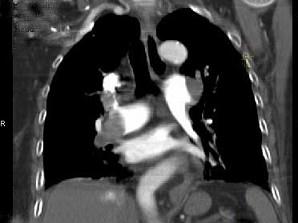

问题 82岁,女性,突发右侧胸痛,呼吸急促,行急诊CT检查,如图所示,请选择最佳答案 ( )

选项 A、肺动脉栓塞 B、肺动脉瘤 C、肺门淋巴结肿大 D、肺动静脉瘘 E、中央型肺癌

答案 A